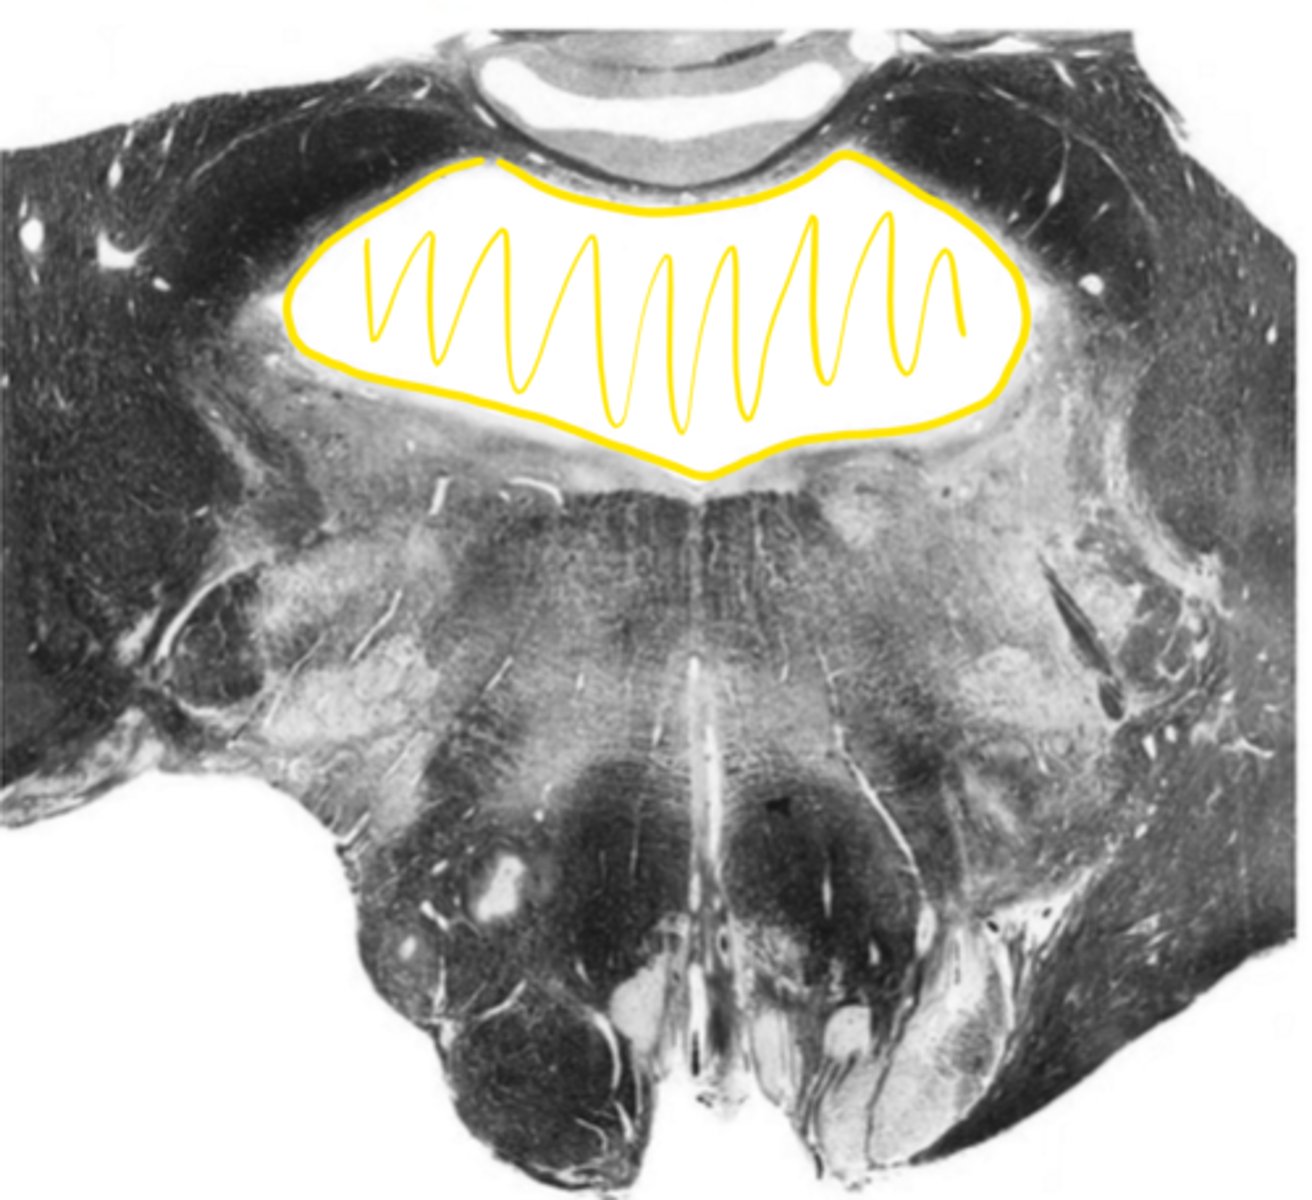

posterior median sulcus

ID the structure

gracile nucleus

ID the light area

gracile fasciculus

ID the dark area

cuneate nucleus

cuneate fasciculus

posterior intermediate sulcus

posterior lateral sulcus

spinal accessory nucleus

descending motor pathways

motor decussation

central gray

central canal